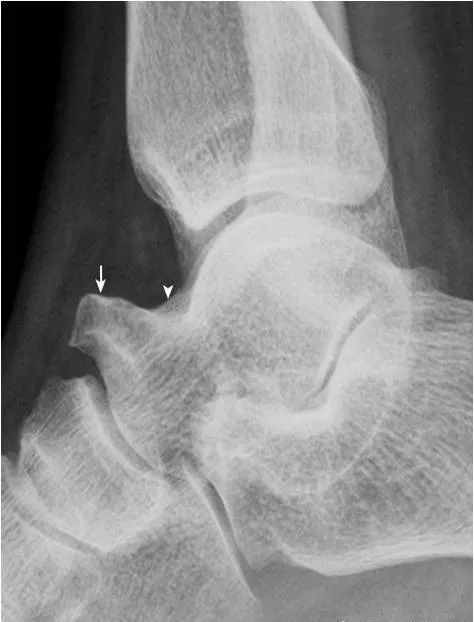

1.跟骨结节骨骺:

形态多样,密度致密(箭),伴裂隙(箭头),为正常表现,勿误认为坏死。

2.Haglund外生骨疣与不典型骨刺:

跟骨后上缘骨刺样突起(箭),属正常变异,称Haglund外生骨疣。穿高跟鞋时可损伤相邻的跟腱,形成Haglund综合征;跟骨结节下缘前突骨刺样突起(箭头),正常人可见,可无临床症状。